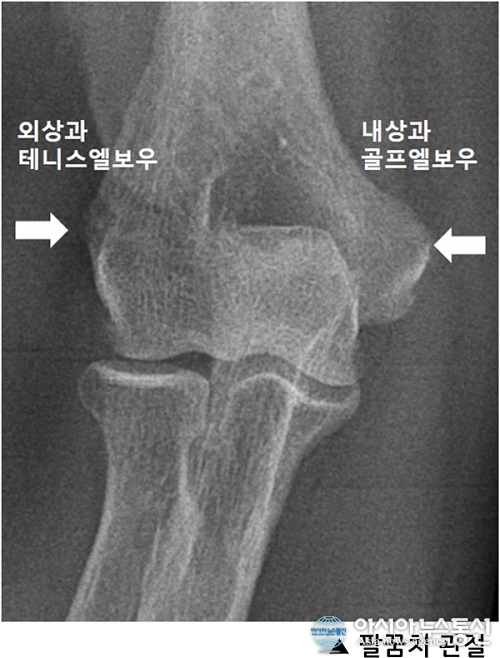

무리한 운동이나 반복되는 팔꿈치 관절의 사용 후에 발생하는 팔꿈치 주변부 통증은 매우 흔하게 접하는 증상이다. 대부분 이런 증상은 2 ~3일 정도 휴식을 하게 되면 사라지게 되는데, 증상이 지속되는 경우에는 테니스 엘보우 (Tennis elbow, 외상과염)나 골프 엘보우 (Golf elbow, 내상과염)와 같은 만성 염증성 통증을 의심해 봐야 한다.

흔히 테니스 엘보우라고 부르는 외상과염은 반복되는 손목 관절의 긴장이나 신전운동에 의해 팔꿈치 관절의 외측에 있는 외상과 부위에 통증이 발생하는 질환이다. 팔꿈치의 외상과 부위는 손목을 신전시키는 근육다발이 시작되는 부위로 손목을 반복적으로 사용하는 행동, 예를 들어 음식물 조리(칼질) 나 걸레 짜는 일, 망치나 드라이버 같은 공구를 다루는 작업, 또는 아이를 오랫동안 안고 있거나 컴퓨터를 장시간 사용하는 경우에 근육의 기시부 힘줄부분에 염증이 생기면서 힘줄이 두터워지고 부분 파열이 생겨 통증이 발생하게 된다.

| 자료사진.(사진제공=좋은아침병원) |